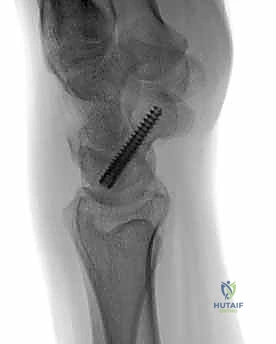

تقنية "التثبيت عن طريق الجلد" (Percutaneous Fixation) هي إجراء جراحي طفيف التوغل (Minimally Invasive). بدلاً من فتح الرسغ، يقوم الجراح بإجراء ثقب صغير جداً في الجلد (لا يتجاوز 3-5 مليمترات). من خلال هذا الثقب، وباستخدام جهاز الأشعة السينية المباشر في غرفة العمليات (C-arm Fluoroscopy)، يتم إدخال سلك توجيهي دقيق، ثم يتم إدخال مسمار خاص يسمى "مسمار ضغط بدون رأس" (Headless Compression Screw) مثل مسمار هيربرت (Herbert Screw).

هذا المسمار العبقري يتم دفنه بالكامل داخل العظم (تحت سطح الغضروف حتى لا يحتك بالمفاصل الأخرى)، ويتميز بوجود أسنان لولبية (Threads) في طرفيه بمسافات مختلفة. هذا التصميم يجعله يسحب طرفي الكسر ويضغطهما معاً بقوة هائلة (Compression)، مما يحفز التئام العظم بسرعة فائقة ويمنع أي حركة بين طرفي الكسر.

يختار الأستاذ الدكتور محمد هطيف المدخل الجراحي بمهارة بناءً على موقع الكسر:

1. المدخل البطني (Volar Approach): من جهة راحة اليد. يُستخدم عادة لكسور منطقة الخصر (المنتصف).

2. المدخل الظهري (Dorsal Approach): من ظهر اليد. يُعتبر الأفضل لكسور القطب القريب، حيث يوفر مساراً أسهل للوصول إلى هذا الجزء العميق بمحاذاة المحور الميكانيكي للعظم.